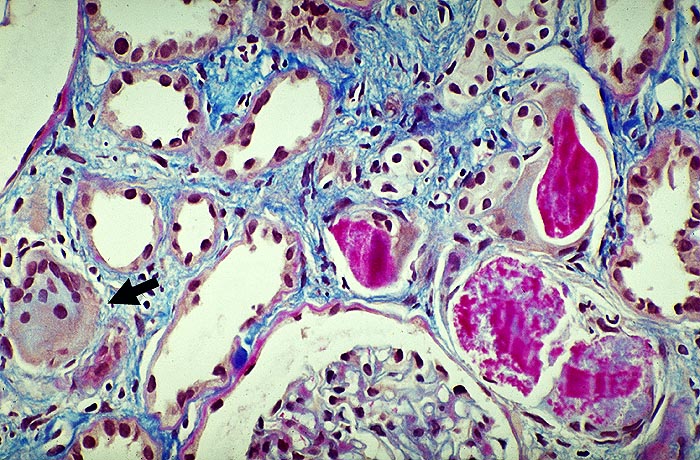

Myelomniere

Die zum Teil krümelig zerfallenen Zylinder werden teilweise von Riesenzellen vollständig umhüllt. An einer Stelle wird das Tubuluslumen durch eine Riesenzelle vollständig ausgefüllt.

Proteinurie ohne nephrotisches Syndrom, da keine Hypalbuninämie. Ausscheidung von Bence-Jones-Protein. Akutes Nierenversagen oder langsam ansteigendes Serumkreatinin. Heute sterben weniger als 10% der Patienten an Urämie wegen verbesserter Hydratation.